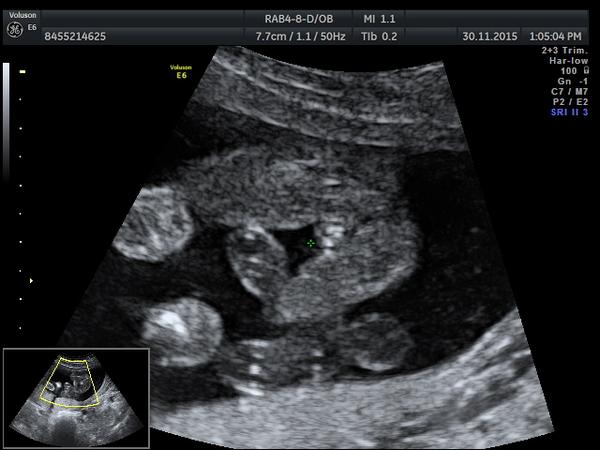

Jinak mne se zda taky hodnd dlouhy, ale vsichni tvrdi, ze pupecni snoura je vedle a zobrazuje se na UTZ jinak, ne tak jasne bile.

ja jsme taky říkala hele to muže byt holka a ten pindík je třeba pupečník.-) ale na genetice řekli jasne kluk když tam to miminko prověřují ze všech stran

@jadupka ty jo to je blba fotka.. Takhle to je kluk, prostě tam něco visí,ale stejně nevim z jakého úhlu na to kouknout..